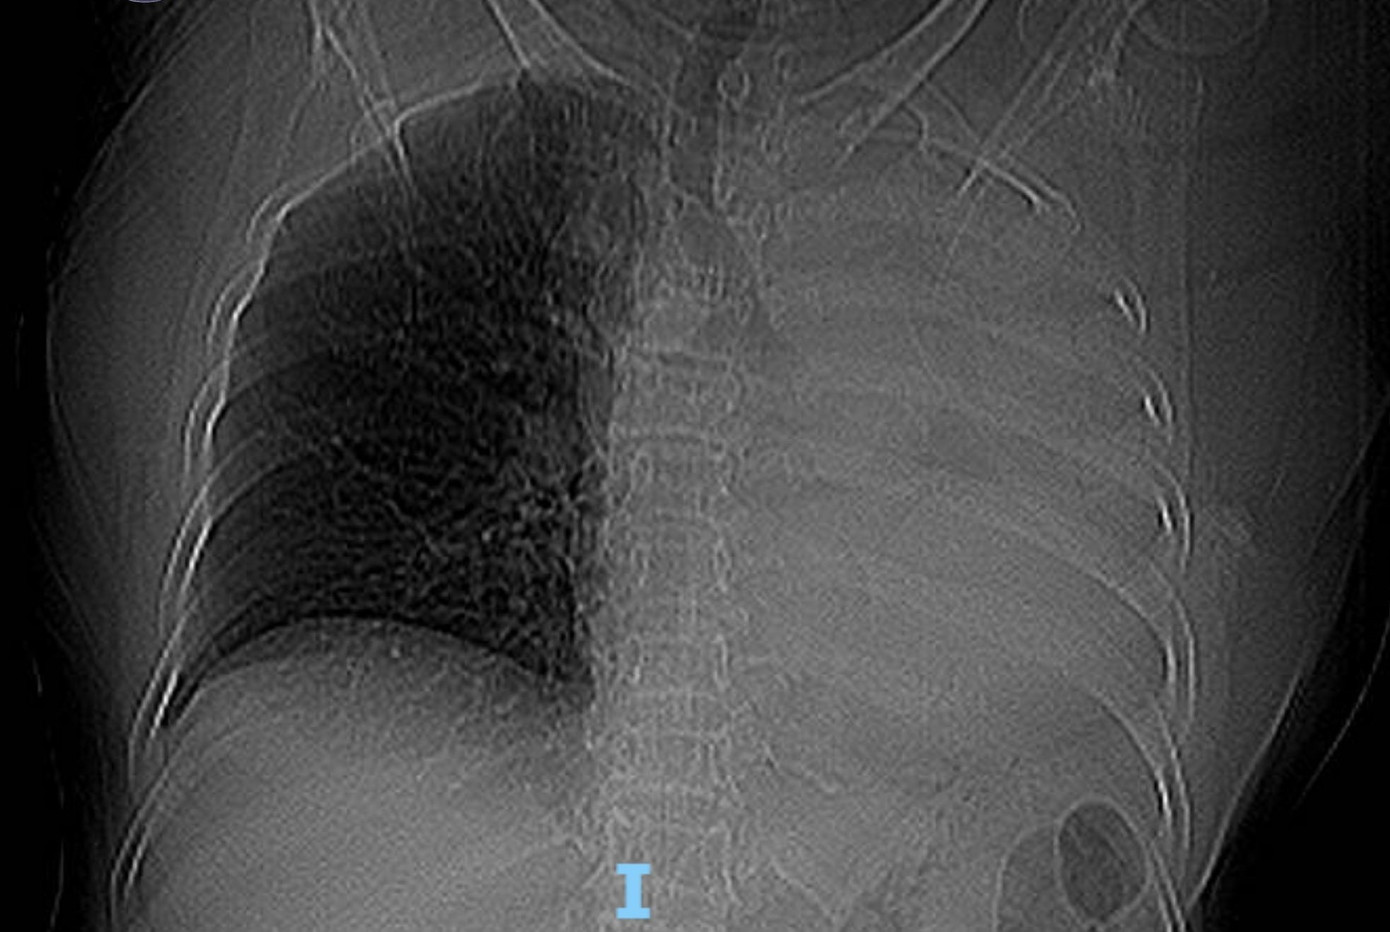

Bệnh nhân là bà T.B. (78 tuổi, trú Đà Nẵng ). Sau khi chụp X-quang ngực, các bác sĩ phát hiện hình ảnh mờ đậm đều toàn bộ trường phổi trái. Kết quả CT cho thấy cụ bà bị xẹp toàn bộ phổi trái do khối tổn thương nằm trong lòng phế quản gốc trái, nghi ngờ u phế quản hoặc dị vật đường thở.

Sặc một viên thuốc, cụ bà xẹp toàn bộ phổi trái- Ảnh 1.

Phim X-quang ngực cho thấy mờ toàn bộ phổi trái.